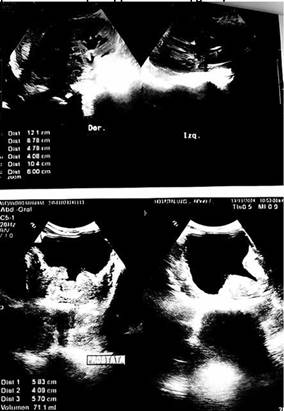

Se completó el estudio con ecografía abdominal, que evidenció múltiples nódulos hepáticos (Figura 2). La ecografía renal y vesical mostró una lesión medular derecha de aproximadamente 7 cm, sugestiva de proceso neoplásico (Figura 3).

FIGURA Nro.3: Ecografía renal que muestra a nivel de riñón derecho a nivel de seno renal una masa tumoral de limites mal definidos de aspecto infiltrativo que mide 7 cm aproximadamente con presencia de flujo Doppler color, vejiga replecionada.

Durante la internación, el paciente presentó hematuria, por lo que se interconsulta con Urología. Se solicitó tomografía abdominopélvica que confirmó tumor renal derecho de aproximadamente 9 cm comprometiendo el seno renal. Posteriormente se realiza la biopsia, la cual confirma un carcinoma renal de células claras, ante estos hallazgos, se derivó el caso a oncología-cuidados paliativos con diagnóstico carcinoma de células claras de riñón metastásico (estadio clínico IV).